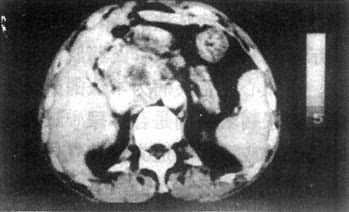

原发性肝癌在T1WI上肝癌的信号强度低于肝,境界常不清楚,有时难以认出。在T2WI上癌瘤较易识别,其信号高于正常肝,常不均匀。癌瘤中心常有不规则更低信号区,肿瘤边缘有时有一低信号的包膜(图4-3-6)。注射造影剂后肝癌信号明显增强,可低于或高于正常肝的信号,境界更为清楚,其中低信号区(出血、坏死、瘢痕)则无强化。若有门静脉内瘤栓,可于低信号的门静脉中出现高信号块影。

图4-3-6 肝癌(MRI)

A、T1WI肝右叶可见大块较低信号区,其内信号不均,轮廓不规

则(↓)。门静脉内可见相同信号强度影像,为癌栓所致(↓)

B、T2WI上述稍低信号区成为稍高信号区(↓),门静脉内癌栓的信

号也增强(↓)